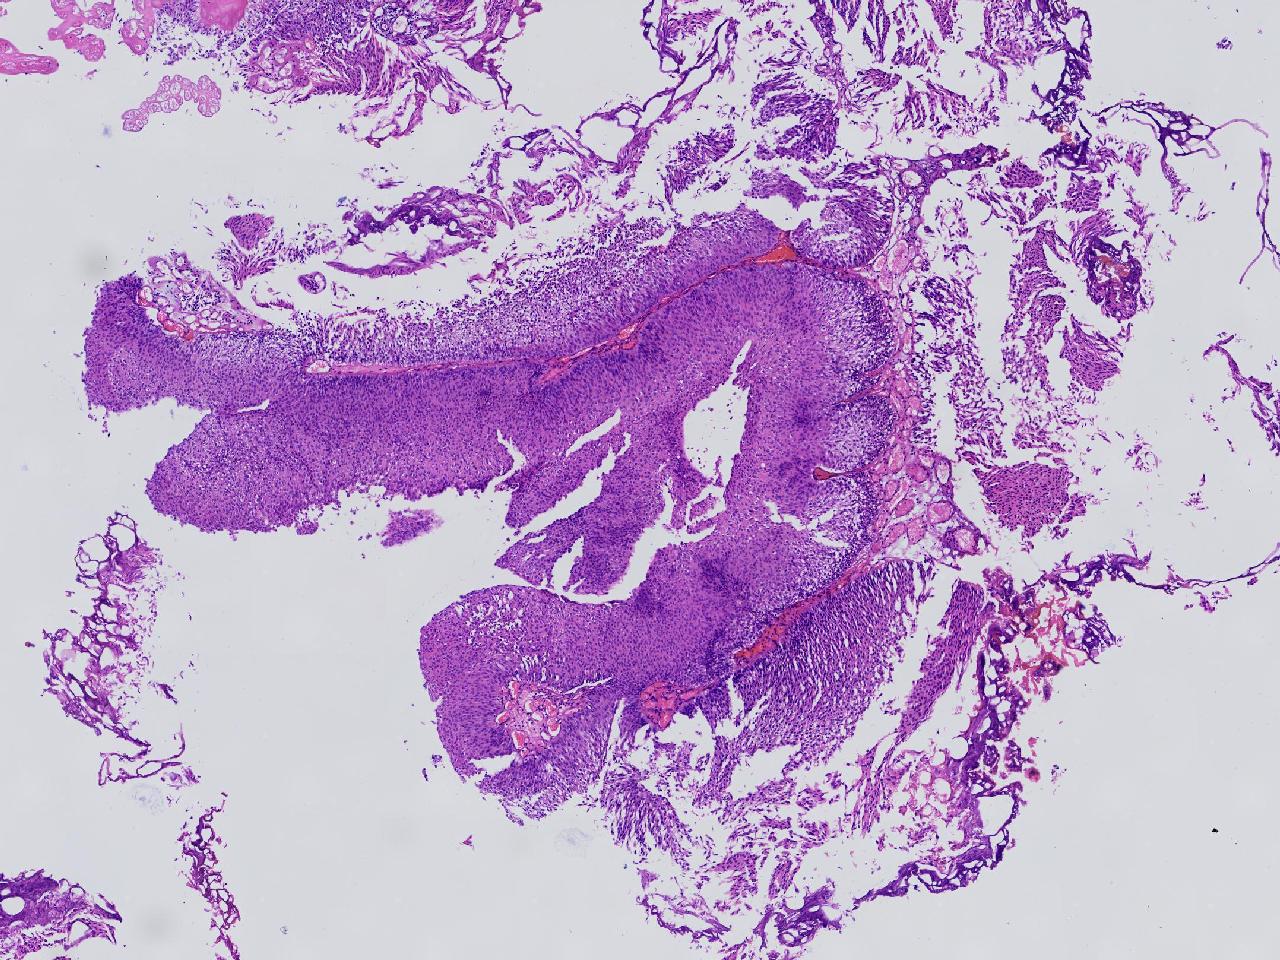

男,79岁,膀胱肿物。

膀胱肿物

灰白色不整形软组织多块,2X1X1厘米。

考虑:乳头状尿路上皮癌

考虑低级别,非浸润。

乳头状尿路上皮癌,低级别。

这几张图片上没有看到明确的浸润。